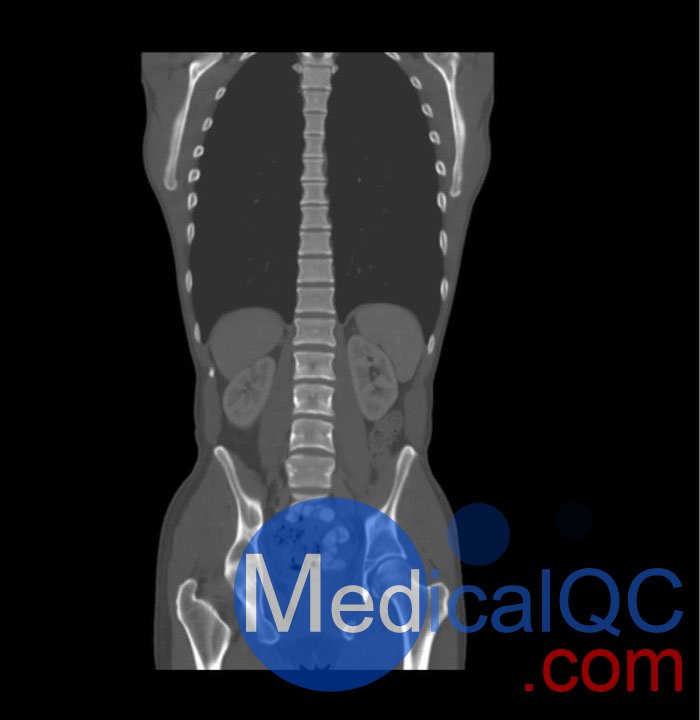

WEK57-01門靜脈期軀干模體,WEK57-01軀干模型模擬了門靜脈期的造影劑增強胸部、腹部和骨盆。它覆蓋了會陰的第二胸椎。

右側(cè)有髂淋巴結(jié)腫塊。

真實模擬脈管系統(tǒng)、骨骼和軟組織,包括肺、心臟、肝臟、膽囊、胰腺、脾臟、腎上腺、腎臟、胃、小腸、結(jié)腸、膀胱和前列腺。

右側(cè)髂外淋巴結(jié)腫塊。

WEK57-01門靜脈期軀干模體,WEK57-01軀干模型成像效果圖: